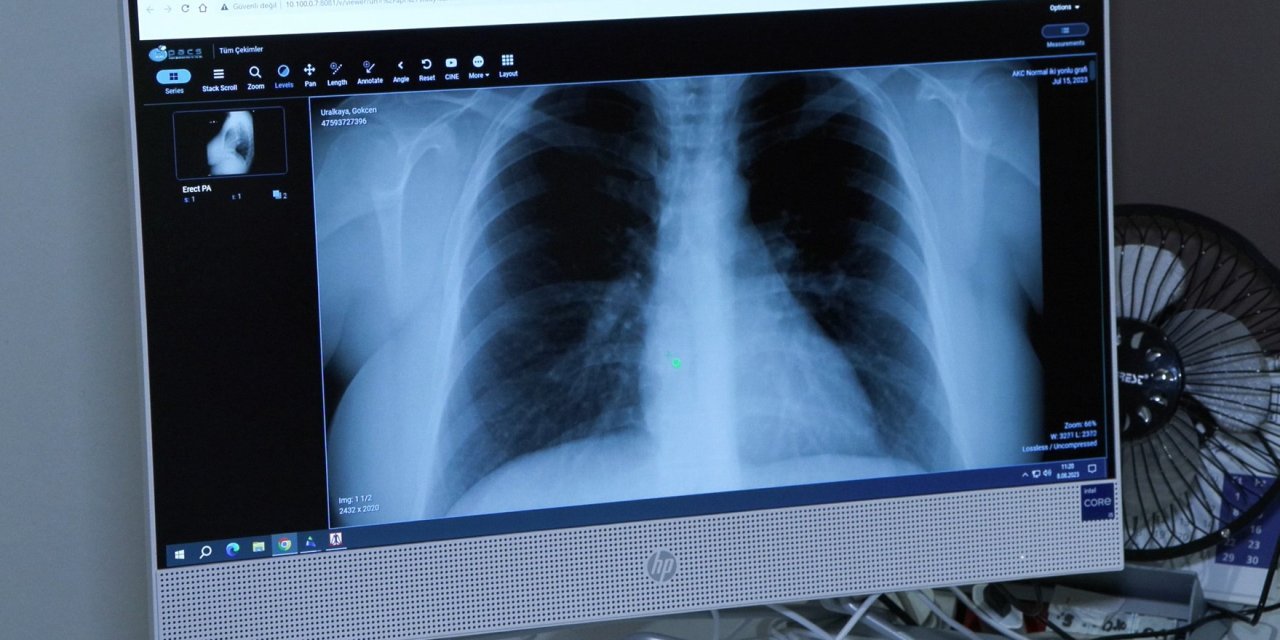

“Afrika sıcaklarıyla akciğer ve alerji hastalıkları da arttı”... Nasıl önlem alınmalı?